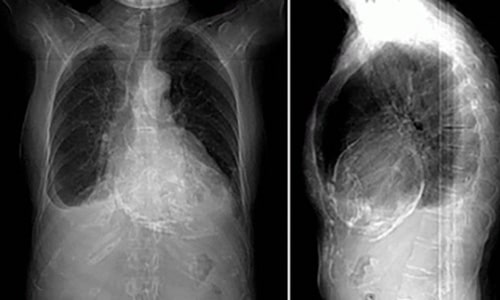

Sou médica formada em 2015 pela Universidade de Ribeirão Preto. Fiz residência de Clínica Médica no Hospital do Servidor Público Estadual de São Paulo e em seguida fiz residência de Cardiologia no Instituto Dante Pazzanese de Cardiologia. Após me especializar como cardiologista optei por me aprofundar em imagem cardiovascular e fiz residência médica em Ecocardiografia também no Instituto Dante Pazzanese, o que me trouxe uma visão muito mais ampla e completa para o domínio e acompanhamento das doenças cardíacas.